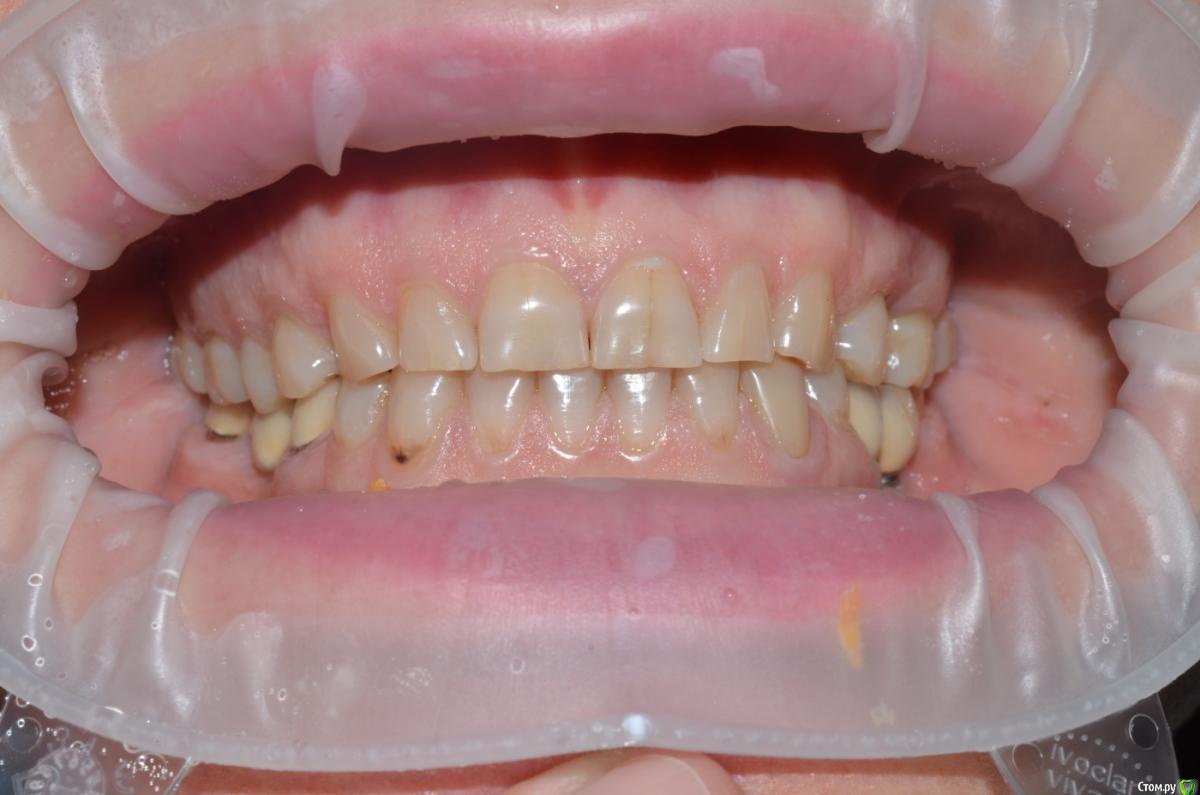

NazranDantist Опубликовано 4 сентября, 2015 Автор Поделиться Опубликовано 4 сентября, 2015 Продолжение кейса. Работа еще не закончена, зуб 25, 35, 36 - аббатменты на подходе, поэтому решили сделать после отпуска пациентки. Фото протокол не соблюдал, курс рубля прыгал, торопился в обменник . Вся работа - имакс на Цереке с редуцированием, фиксация - фронт на чойс, боковые - У-200. Ссылка на комментарий

CHEREDNICHENCO Опубликовано 12 сентября, 2015 Поделиться Опубликовано 12 сентября, 2015 Режет глаз смещение цл, оптг необходимо определенно, хотя бы для оценки состояния тттз и периапикальных тканей в 4 секторе.... Индикатор кариеса используете в работе???.... А зачем в 3 секторе оставили временную конструкцию?! Или это постоянная???..... В десятых- эстетически не вяжется соотношение нижних к верхним... PS: В связи с определенным географическим положением, КНДР находиться в 1 км. 44 м. от места моей работы! и хочу сообщить Вам,- уровень их работ растет от из года, в год! Ссылка на комментарий

NazranDantist Опубликовано 12 сентября, 2015 Автор Поделиться Опубликовано 12 сентября, 2015 Режет глаз смещение цл, оптг необходимо определенно, хотя бы для оценки состояния тттз и периапикальных тканей в 4 секторе.... Индикатор кариеса используете в работе???.... А зачем в 3 секторе оставили временную конструкцию?! Или это постоянная???..... В десятых- эстетически не вяжется соотношение нижних к верхним... PS: В связи с определенным географическим положением, КНДР находиться в 1 км. 44 м. от места моей работы! и хочу сообщить Вам,- уровень их работ растет от из года, в год! А что делать с центральной линией, если она смещена? Кариес индикатор для чего? Про времянки в 3-ем секторе уже написал " Работа еще не закончена, зуб 25, 35, 36 - аббатменты на подходе". Оценка периапекальных тканей проводилась. Ссылка на комментарий

CHEREDNICHENCO Опубликовано 13 сентября, 2015 Поделиться Опубликовано 13 сентября, 2015 Кариеса нет.DSC_0643.JPGСмещение естьПо фото, когда зубные ряды находятся в контакте- смещение есть! Но на первых фото, когда НЧ находиться в состоянии относительного физиологического покоя, смещения нет! ТО делаю вывод, смещение возникает в результате неправильного соотношения жевательных поверхностей зубов. Ссылка на комментарий